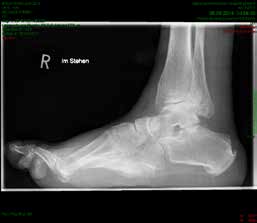

So erhielt ein 67-jähriger männlicher Patient nach operativer Versorgung mittels Fixateur externe neben einer Entlastung nur eine di_CAP-Therapie. Als Hauptdiagnose wurde eine sekundäre Fußfehlstellung in Pes-cavovarus-Position mit chronischem Ulcus am rechten Fußrand bei diabetischer Neuroosteoarthropathie festgehalten (Abb. 2); relevante Nebendiagnosen waren eine pAVK und diabetische Nephropathie. Als operative Therapie wurde eine Stellungskorrektur mit dem Hoffmannschen Fixateur externe durchgeführt (Abb. 3). Intraoperativ konnte eine bakterielle Besiedlung mit Escherichia coli, Enterococcus faecalis und Enterobacter cloacae nachgewiesen werden. Während des stationären Aufenthaltes wurde der Patient zweimal wöchentlich mit di_CAP behandelt. Nach seiner Entlassung erfolgte die Einbestellung zur di_CAP-Therapie nach der 4., 6. und 10. postoperativen Woche. Dabei wurde vor jeder Wundbehandlung ein Abstrich für eine mikrobiologische Untersuchung genommen. Im Verlauf kam es zu einer guten Wundheilung des anfänglich 3 × 5 cm messenden plantaren Ulcus, und in der 10. postoperativen Woche ließ sich eine fast vollkommene Wundheilung beobachten (Abb. 4). Ab der 1. postoperativen Woche war in den mikrobiologischen Abstrichen nur noch E. faecalis nachweisbar, und ab der 4. Woche konnte im Ulcus kein Keim mehr nachgewiesen werden. Aufgrund der geringen Patientenanzahl und der unregelmäßigen Wiedervorstellungen der Patienten konnte die Kohorte nicht suffizient im Verlauf beobachtet werden, um genügend Daten für eine prospektive Studie zu generieren. Die klinischen Erfahrungen der Verfasser decken sich jedoch mit Ergebnissen bisheriger Arbeiten zur di_CAP-Therapie.